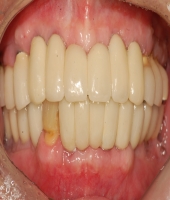

| ● 진료과목 : [임플란트] 치주환자의 임플란트 보철치료

| ● 내용 : 50대 치주환자의 임플란트치료. |